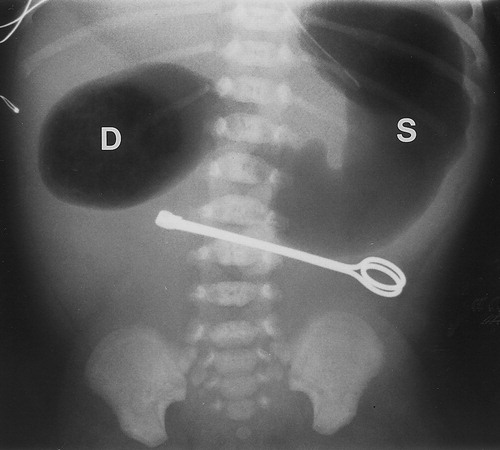

Duodenal atresia is diagnosed with a characteristic finding of a ‘____’ on abdominal x-ray

double bubble